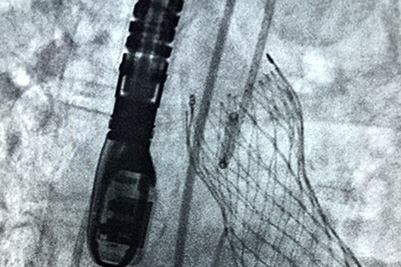

Transcatheter Aortic Valve Replacement (TAVR)

Transcatheter Aortic Valve Replacement, TAVR for short, has been implanted in more than 70,000 patients worldwide.